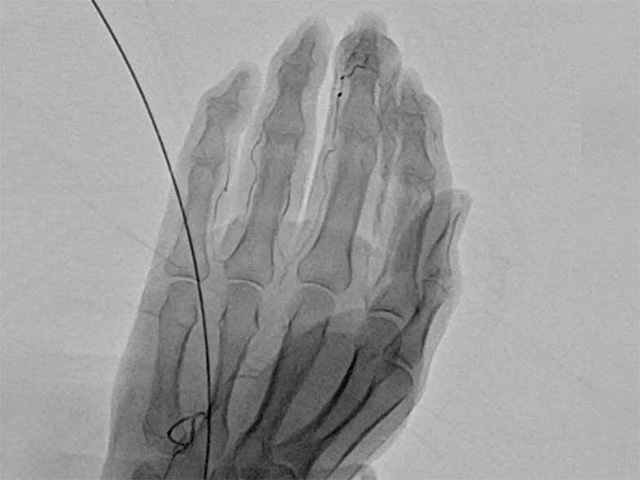

簡易動注療法とは、超音波(エコー)で血管の位置を確認しながら、手首や足首などの動脈に細い針(またはチューブ)を挿入し、薬剤を注入する治療法です。

この治療の目的は、痛みの原因と考えられる“新生血管(いわゆる「モヤモヤ血管」「異常血管」)”の血流を減らすことで、炎症を鎮め、慢性的な痛みを軽減することにあります。

エコーで血管を確認しながら、局所麻酔を行い、手首・足首などの動脈に細い針(チューブ)を挿入。薬剤を注入します。処置はおよそ10分前後で終了。